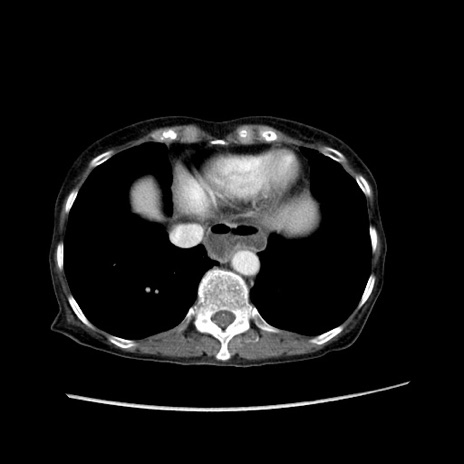

冠状断像